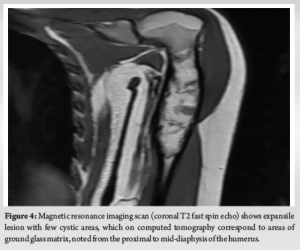

A 22-year-old female patient presented with complaints of pain in her left arm on and off for the past 2 years, which had been aggravated over the last 1 month. Pain is an insidious, progressive, non-radiating, dull aching type, aggravated on physical activity, relieved on rest. Patient had an alleged history of trauma 6 years back (skid and fall at her residence) sustaining injury to left arm and diagnosed to have a humerus fracture and lytic lesion. For which she was treated conservatively at an outside hospital. After 2 months of the fracture, the patient sustained again fracture over the same site and opted for conservative treatment. After 2 months of refracture aspiration (~50 mL) under CARM Guidance at SBMCH was done. On examination, no scar, sinus, or obvious swelling was noted. No soft tissue/bony tenderness seen. Range of motion (shoulder and elbow) was full and free without distal neurovascular deficit (DNVD). Blood investigations were carried out and found to be normal. X-ray (Fig. 1) showed mixed ill-defined lytic expansile lesions with a narrow zone of transition over the proximal 2/3rd of the left humerus. After the surgical procedure, the curettage bone was sent for histopathology (Fig. 2) and reported as fungal infection.

This case was reported due to its rarity and diagnostic complexity. While fibrous dysplasia is a known benign lesion with distinct radiological features, this case demonstrates that fungal infections can closely mimic such lesions both clinically and radiographically. The unexpected histopathological finding of fungal spores in an immunocompetent patient underscores the importance of maintaining a broad differential diagnosis when evaluating bone lesions. The incidence of fungal infection of bones and joints is usually low and rare. Invasive fungal infections are more likely to be associated with a rising population of immunosuppressed patients [7], and are also seen in patients with several comorbid conditions. Patients under steroid treatment are likely to be immunosuppressed and are prone to acquiring infections. Species such as Candida and Aspergillus are the most common causative organisms [8]. Candida, being an endemic dimorphic fungus, is accountable for an enormous number of cases globally. Fungal infections are commonly transmitted through the hematogenous route. Transmission from contiguous infection, or by direct inoculation following trauma or surgery, is also noted. Clinically, adults present with mild features, often without fever or a rise in inflammatory markers. Children may have features of vertebral osteomyelitis, which differ from adult presentations [9]. Due to the dormant nature of symptoms in adults, diagnosis is often delayed. Diagnosis is based on tissue culture, tissue histology, and clinical correlations. In this case, the X-ray findings (Fig. 1, 2) mimicked fibrous dysplasia, showing a mixed expansile lesion with ground-glass opacity. The patient was clinically and radiologically (Fig. 3-5) diagnosed to have fibrous dysplasia. However, histological examination revealed a fungal infection. Therefore, to avoid misdiagnosis, tissue culture and histology are necessary in similar presentations. Once diagnosed, appropriate antifungal medication and often surgical debridement are required.

Fibrous dysplasia is characterized by the replacement of mature bone marrow with an immature abnormal matrix by fibro-osseous growth. Due to somatic mutation, it affects woven bone and leads to failure of turning into lamellar bone [10]. This condition often has no symptoms and is an incidental finding, usually presenting as a pathological fracture. Radiographically, a clearly circumscribed lesion with a narrow zone of transition can be appreciated. Computed tomography and magnetic resonance imaging (Fig. 3-6) are also found to be useful. Fibrous dysplasia is mostly treated symptomatically – such as managing pathological fractures or with simple palliative care [11,12]. Curettage, bone grafting, and fixation techniques are also used for the correction of deformities. Medically, bisphosphonates may be supplemented with other supportive treatments.